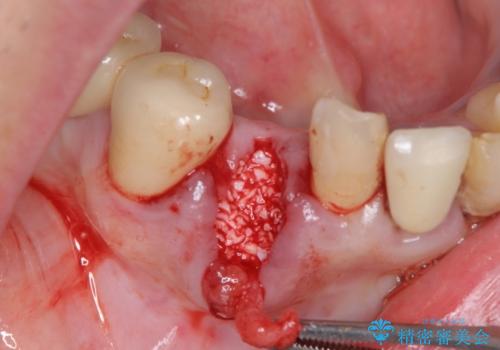

抜歯後、インプラントによる審美・機能改善を希望されたのでインプラント埋入に先立ち吸収した骨の再生を計画します。

歯を失う原因が虫歯や根尖病変などはなく、歯周病や歯の破折等周囲の骨を吸収する原因の場合はインプラント治療を行うに先立ち骨の造成が必要なことがあります。